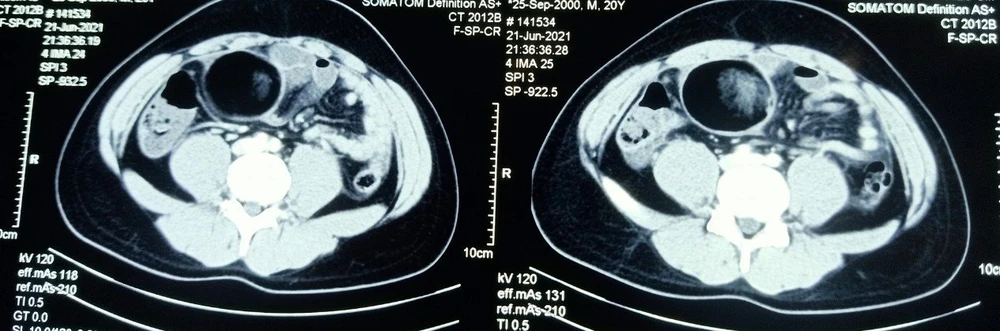

(PLO)- Qua chụp cắt lớp, các bác sĩ phát hiện bệnh nhân A. có một khối u tinh hoàn đường kính 7cm trong ổ bụng...

Sau đó A. đến khám tại Bệnh viện Vũng Tàu ( Bệnh viện Lê Lợi cũ mới đổi tên-PV) và được các bác sĩ khám, tiến hành cho chụp cắt lớp. Qua kết quả chụp cắt lớp bác sĩ phát hiện A. có một khối u có đường kính 7cm. Khi thăm khám lâm sàng các bác sĩ phát hiện bệnh nhân chỉ có một tinh hoàn bên trái dưới bìu, trong bìu bên phải không thấy tinh hoàn.

Hình chụp phim khối u do BV Vũng Tàu cung cấp